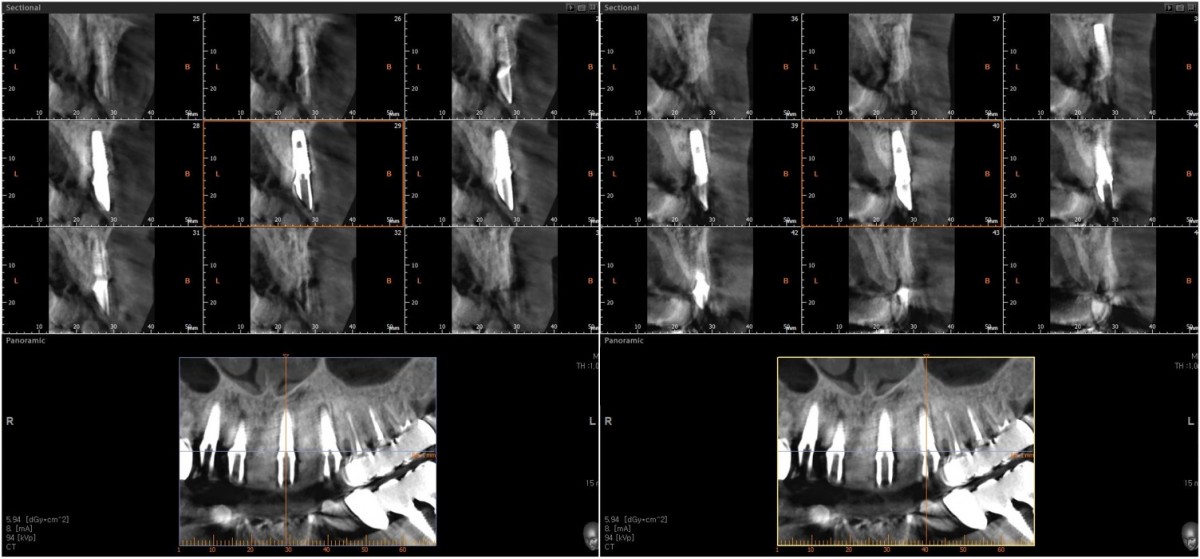

▲Implant placement GBR

▲GBR(Xenograft).